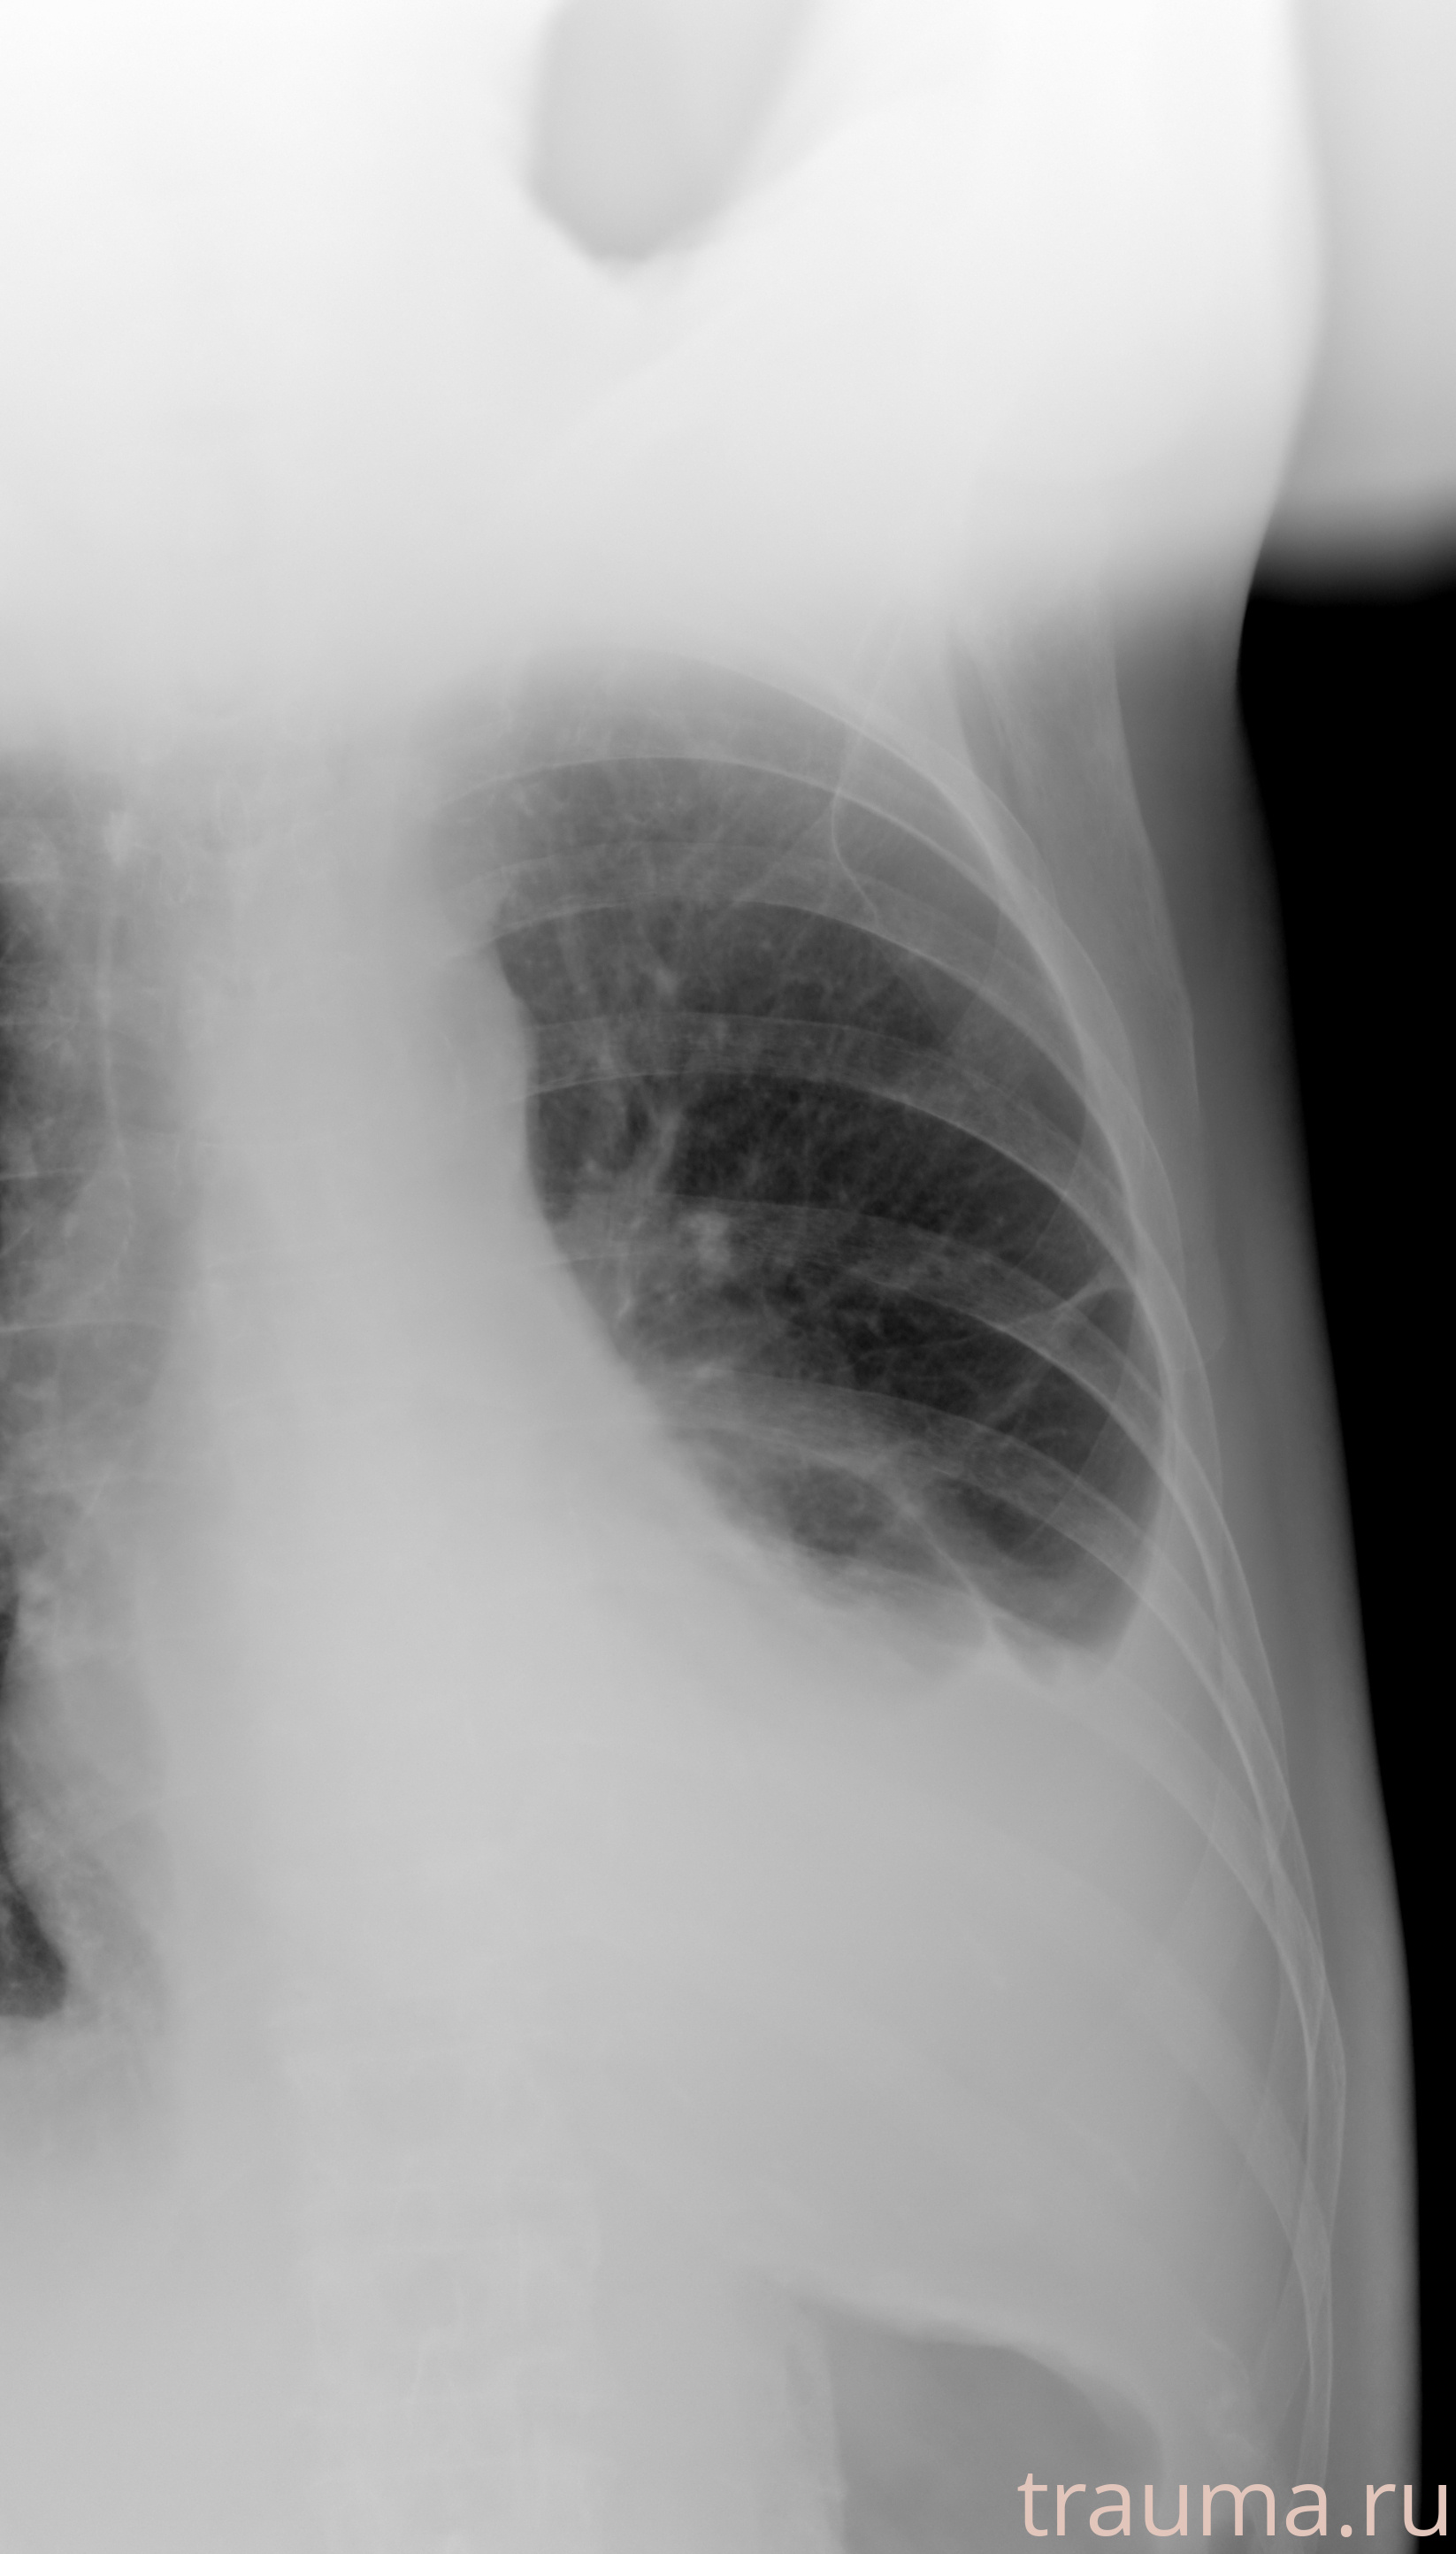

Рентген на дому: по вашему адресу приезжает врач-рентгенолог, травматолог-ортопед с мобильным рентгеновским аппаратом, проводит диагностику травмы или заболевания, делает необходимые рентгенограммы, дает рекомендации по дальнейшему лечению. Получить качественные снимки в домашних условиях возможно благодаря уникальной методике, разработанной МосРентген Центром для института  Склифосовского